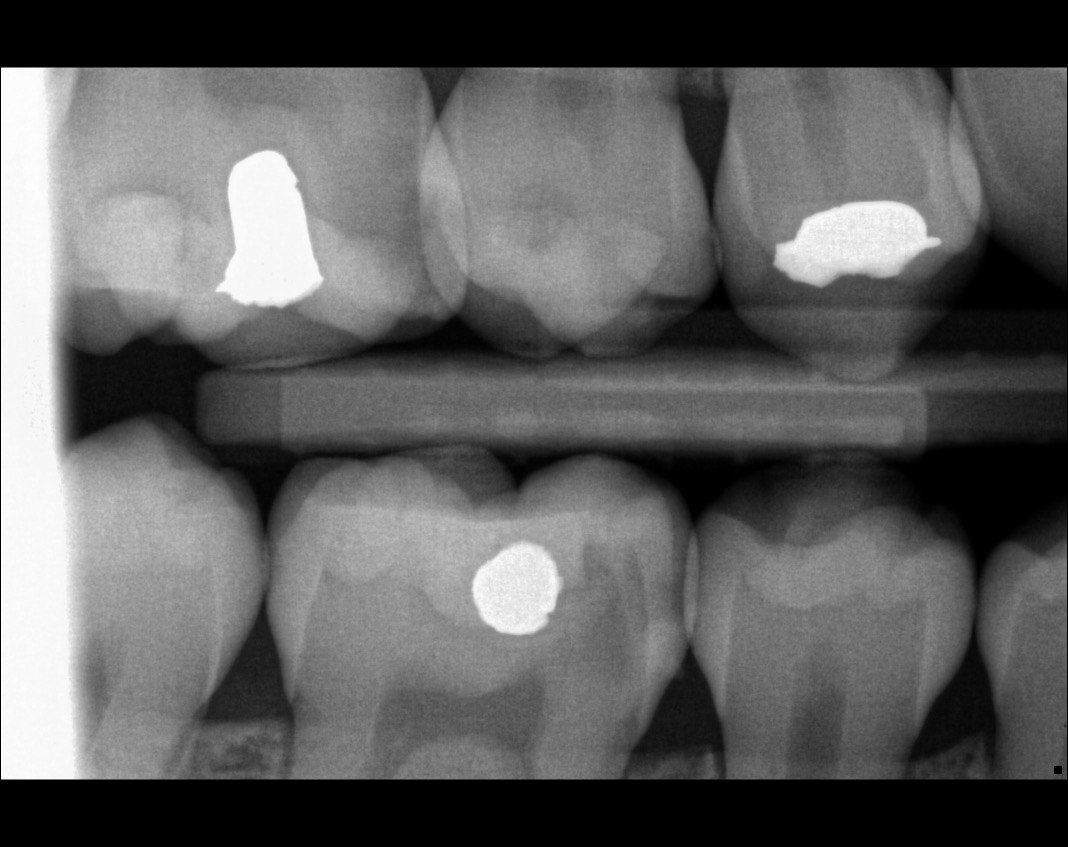

Question 7: What are the options associated with the distal surface of the tooth # 2.1 and mesial surface of the tooth # 2.2 respectively?

Question 8: What is the condition associated with the occlusal surface of the tooth # 1.6?

Question 9: What is the condition associated with the mesial and distal surfaces of the tooth # 1.4 respectively?

Question 10: What is the condition of the distal surfaces of the teeth # 1.5 and 1.6 respectively?